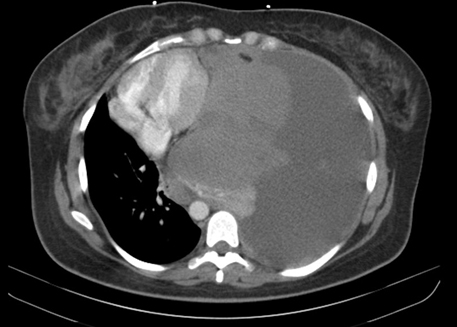

On the first day of hospital presentation, imaging in the ED included chest radiograph (CXR) (Figure 1) and computed tomography (CT) (Figure 2). Imaging revealed a mediastinal mass measuring 10 × 12 × 15 cm with a heterogeneous composition, along with a severe tension hydrothorax and mediastinal shift to the right with a massive left-sided pleural effusion.

Figure 2: Computed tomography (CT) imaging of the chest upon arrival to the emergency department that revealed a severely abnormal examination prior to emergent thoracoscopy. Imaging revealed mediastinal mass 10 × 12 × 15 cm with heterogenous composition and a severe tension hydrothorax with massive left-sided pleural effusion and severe mediastinal shift to the right by approximately 7–10 cm. Pleural effusion extended inferiorly into the abdomen resulting in mass effect on the visualized liver, pancreas, and left kidney.